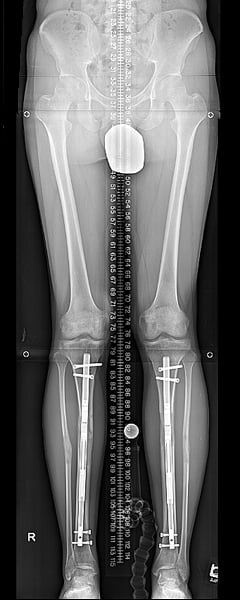

Femurs at end of distraction.

The lengthening device utilized most often at HSS contains two metal rods, one inside the other, and a small magnet and gears. An external magnet used by the patient connects to the internal magnet within the rod, which twists the gears and causes the two rods to separate. This "distraction" phase happens in very small increments, controlled by the surgeon and the patient, so that healing of the new bone growth ("consolidation") occurs during the lengthening.

Stature lengthening surgery is a procedure to increase your natural height by lengthening the bones in your legs. The lengthening occurs through a controlled break in the bone followed by gradual lengthening. During the gradual lengthening, the body attempts to heal the bone by adding new bone structure. When the lengthening is complete and the new bone structure heals, the bone is then longer, and thus your height has increased! This is usually done in each thigh bone (the femur) because of its excellent capacity to heal.

However, in some cases, the lower leg bone (tibia) may be lengthened instead of or in addition to the femur. In such cases, the fibula is also cut and stabilized to the tibia at both ends using screws as sutures, so that it lengthens as well. The fibular lengthening does not require a separate device but is achieved by the tibial lengthening nail.

How does the lengthening device work?